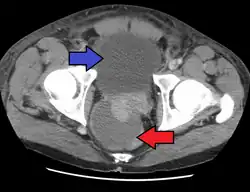

Severely ill patients may need hospitalization, while nontoxic patients can be treated at home with bed rest, analgesics, stool softeners, and hydration. Men with acute prostatitis complicated by urinary retention are best managed with a suprapubic catheter or intermittent catheterization. Lack of clinical response to antibiotics should raise the suspicion of an abscess and prompt an imaging study such as a transrectal ultrasound (TRUS).[7]